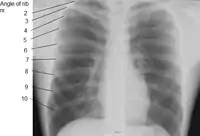

X-ray image of a human chest, with ribs labelled